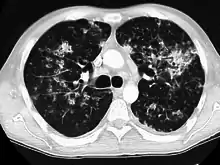

CT image showing crazy paving pattern of ground-glass opacities in both lungs.

Crazy paving

The crazy paving pattern may occur when there is both interlobular and intralobular widening. This sometimes resembles a road paved with irregular bricks or tiles. It is typically diffuse, involving larger areas of one or multiple lobes. There are a variety of potential causes, including Pneumocystis pneumonia, late-stage adenocarcinoma, pulmonary edema, some types of idiopathic interstitial pneumonias, diffuse alveolar hemorrhage, sarcoidosis, and pulmonary alveolar proteinosis.[6] COVID-19 has also been shown to occasionally cause GGOs with a crazy paving pattern.[11]